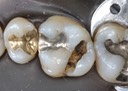

Joe Cha #3 casting on model